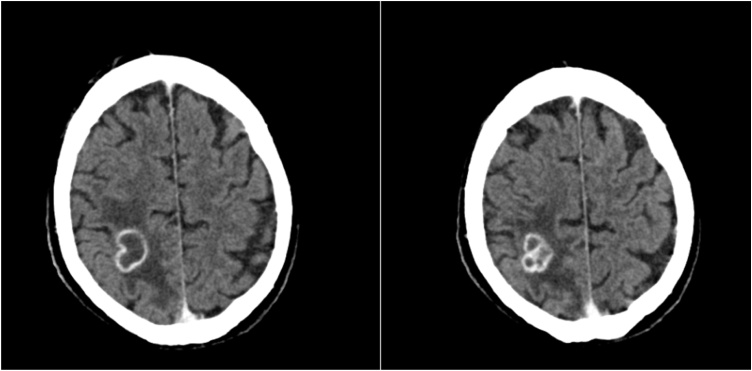

Cerebral computed tomography (CCT) constituted spheres of atypical bleeding in both hemispheres and extra-axial blood formations in the left hemisphere with no dynamics in repeated CCT after six hours. Finally, contrast CCT found two hypointense parietal and occipital areas with scalloped microvascular blood impurities, with an hyperintense 2.5 cm ring enhancement with poorly definable circumvent at the right upper parietooccipital region including a surrounding edema (Fig. 1).

Fig. 1.

CT Scan with contrast with a 2.5 cm lesion at the right upper parietooccipital region.

This diagnosis of BA precluded the patient from prompt HTX, which was urgently indicated for the LVAD system infection. With antibiotic therapy of Rifampicin and Ceftriaxone the patient experienced relief of his visual symptoms as well as general condition and clinical presentation improved. Ceftriaxone was administered in dosage of 4 g daily to facilitate Ceftriaxone to pass hemato-encephalic barrier to reach BA. Contrast CCT after one week of treatment in our center showed slightly diminished lesions (19 × 18 × 20 mm) with an additional slight regression of the surrounding edema encouraging us to pursue the antibiotic regime to achieve HTX listing for this patient (Fig. 2).